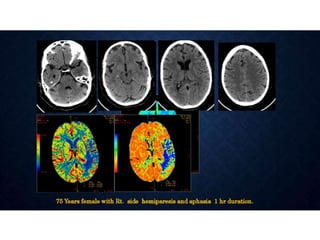

CTP IN STROKE •• Stroke is a leading cause of mortality and morbidity in the developed world. • • The goals of an imaging evaluation are • I. to establish a diagnosis as early as possible • II. to obtain accurate information about the intracranial vasculature • III. to identify critically ischemic or irreversibly infarcted tissue (“core”) and to identify severely ischemic but potentially salvageable tissue (“penumbra”). • This information can guide triage and management in acute stroke.